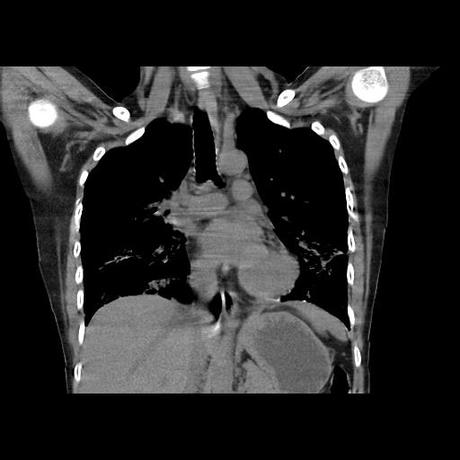

Se realiza volumen de tórax en fase simple, desde los opérculos torácicos hasta los hemidiafragmas, observándose:

El parénquima pulmonar con areas parcheadas difusas en vidrio despulido combinadas con otras areas hipodensas de baja atenuación debidas a atrapamiento aéreo y engrosamiento intersticial y zonas de fibrosis de predominio en lóbulos medios e inferiores de ambos pulmones.

En los cortes valorados de abdomen hígado, bazo y páncreas sin evidencia de alteraciones, glándula suprarrenal izquierda con imagen ovalada, bordes definidos, homogénea, mide 11 mm en probable relacion a adenoma.

- LOS HALLAZGOS PUEDEN ESTAR EN RELACIÓN A NEUMOPATIA INTERSTICIAL PROBABLE ETIOLOGIA HIPERSENSITIVA VS AUTOINMUNE/BACTERIANA/FUNGICA.

- PROBABLE ADENOMA DE SUPRARRENAL IZQUIERDA.